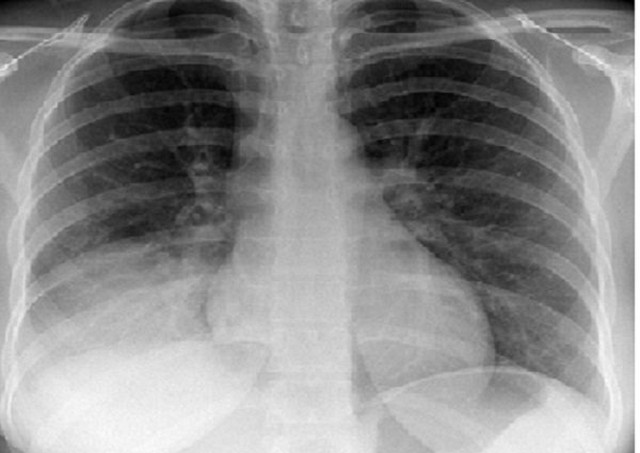

Hội chứng đông đặc phổi là một bệnh lý của nhu mô phổi có thể được phát hiện thông qua các phương pháp lâm sàng và hình ảnh chụp X-quang. Có rất nhiều nguyên nhân có thể dẫn đến tình trạng bệnh này, do đó việc chẩn đoán bệnh yêu cầu sự kết hợp giữa việc thăm khám lâm sàng và thực hiện các xét nghiệm cận lâm sàng. Bài viết dưới đây sẽ giới thiệu cho bạn đọc những thông tin cơ bản nhất về hội chứng đông đặc phổi.